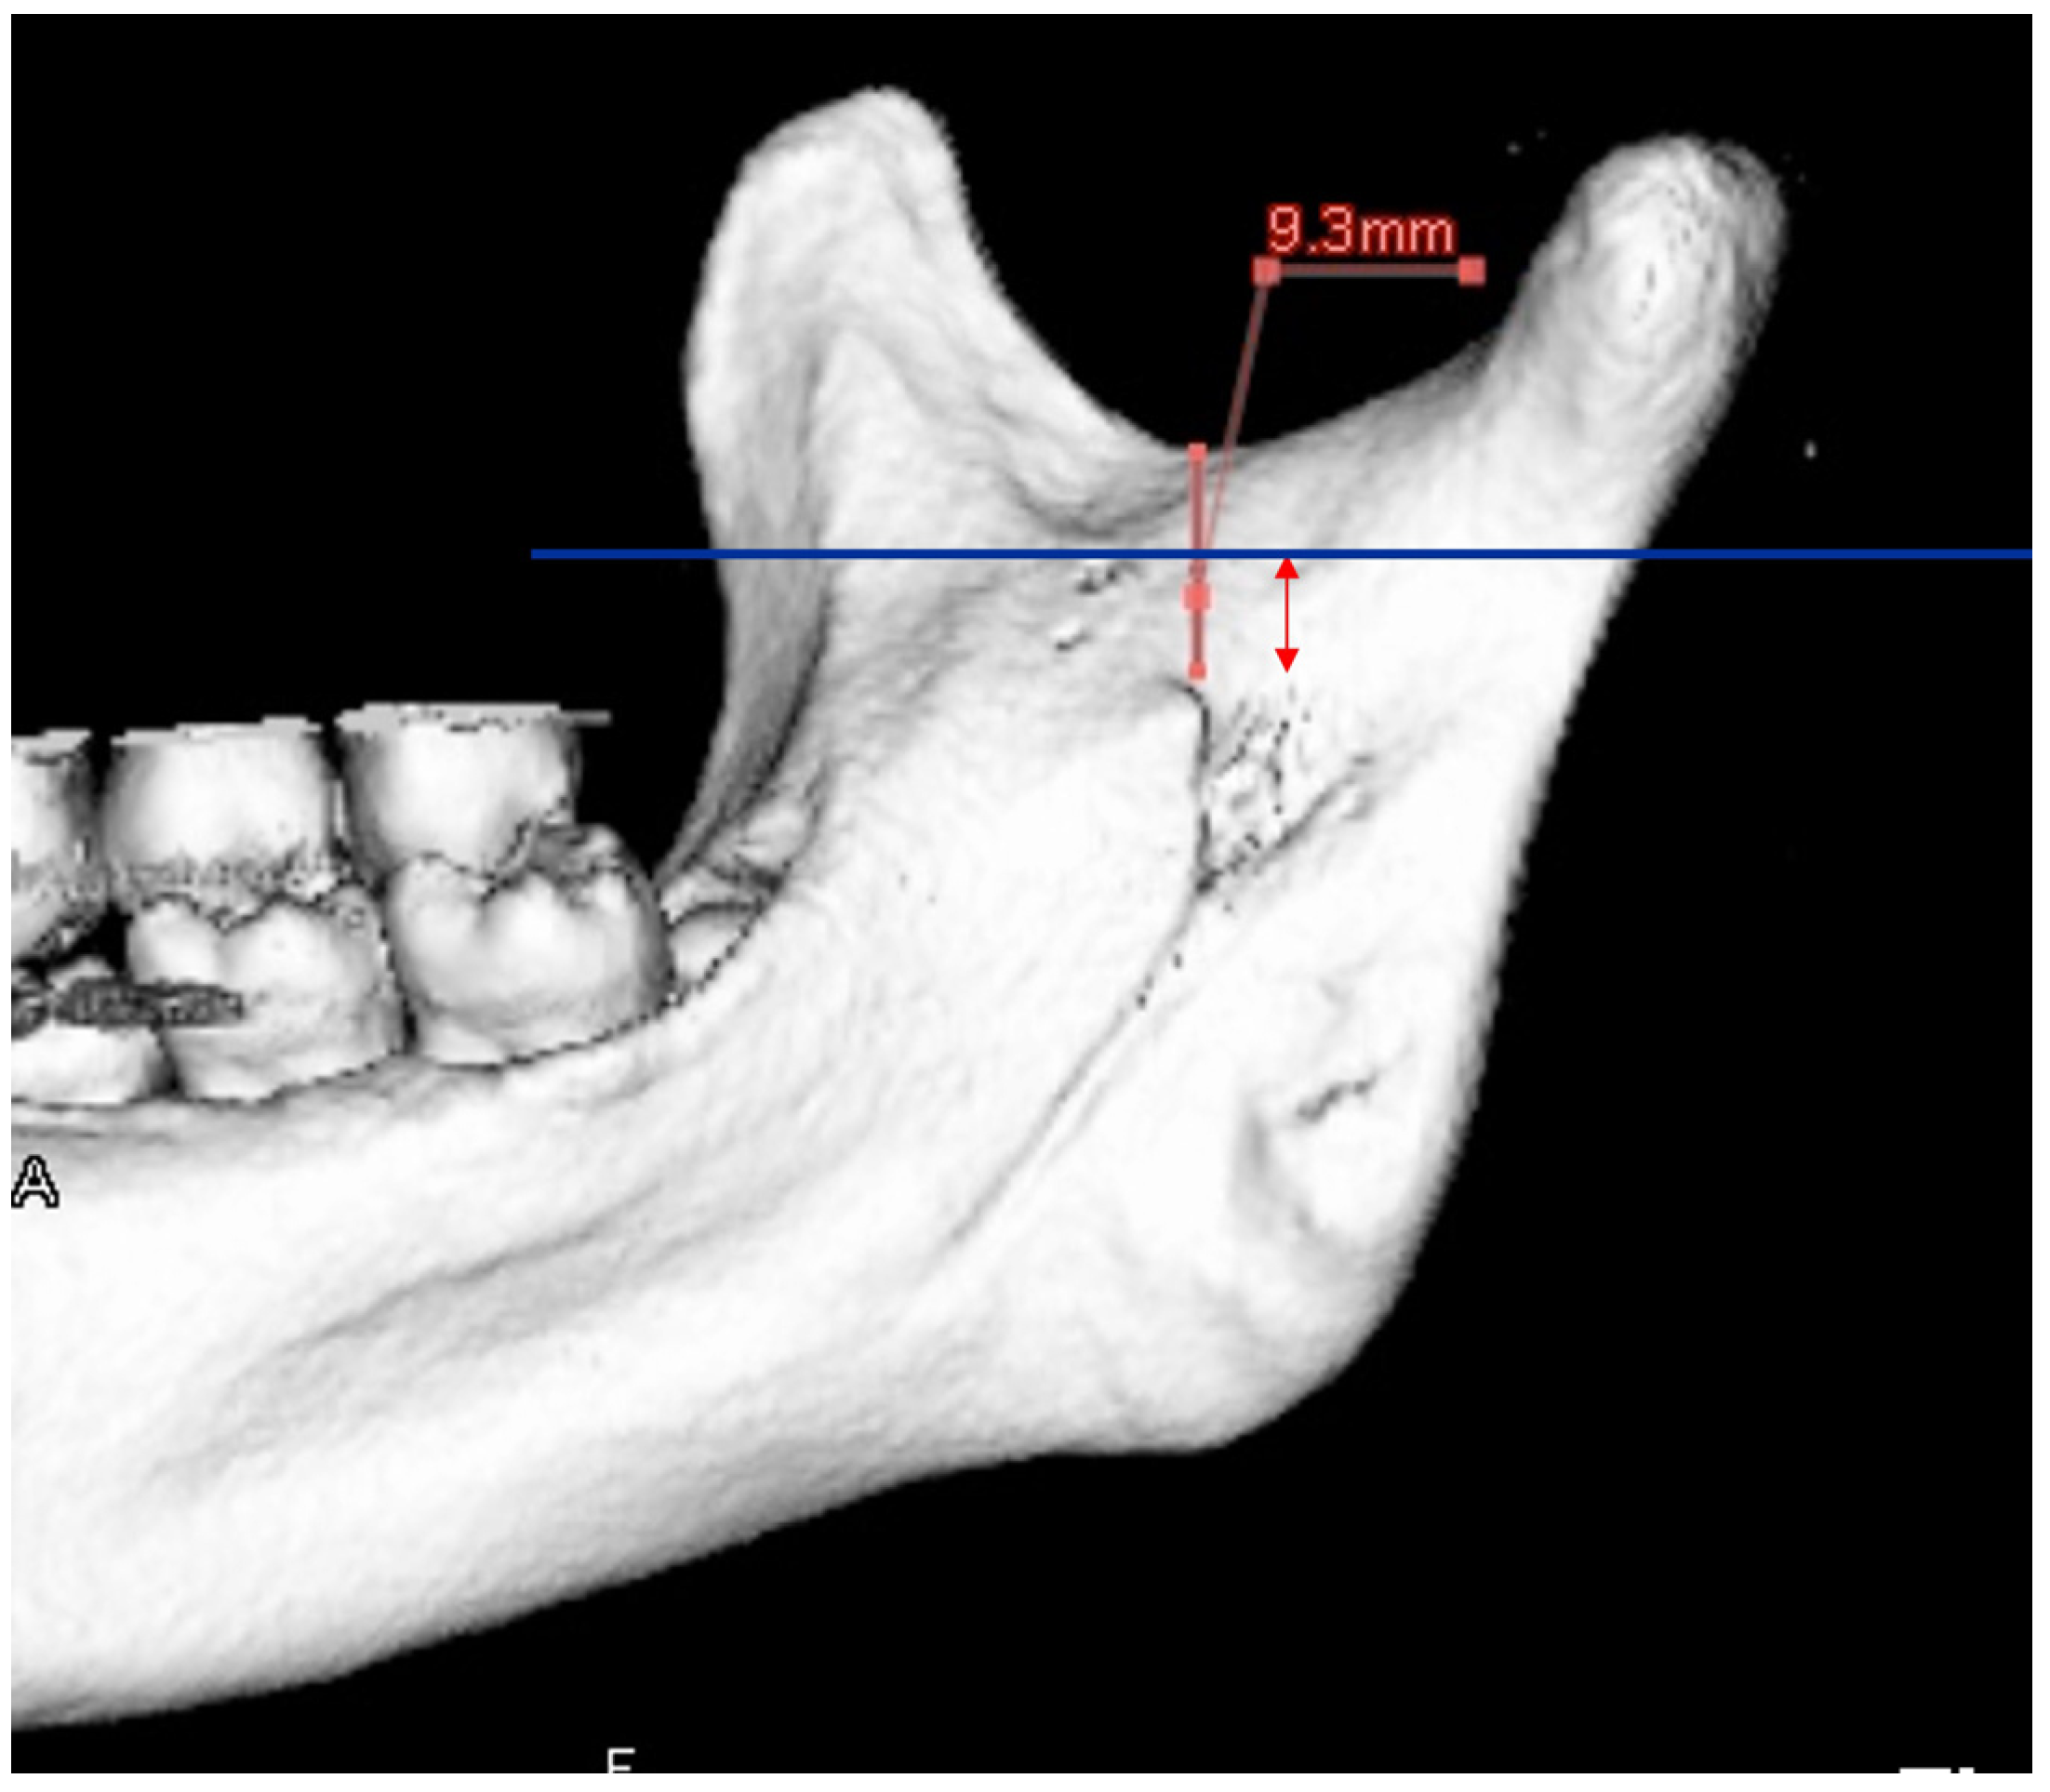

| Setting the osteotomy line 1. Evaluation of the position of the mandibular canal and surrounding bone quality Presence or absence of mandibular canal bifurcation and course of resection site Distance from the buccal wall of the mandibular canal to the buccal cortical bone margin Bone quality around the mandibular canal (CT number) 2. Distance from the mandibular notch to the lingula Whether it is 14 mm or more 3. Morphology of the mandible and variation in cortical bone thickness Cortical bone thickness in the medial osteotomy area and lateral osteotomy area Enhanced safety through improved visibility 1. Medial curvature of the mandibular ramus Mandibular ramus is straight or strong curvature 2. Course of small blood vessels along the bone surface Depression of the buccal-lingual cortical bone from the mandibular fossa to the mandibular ramus region, trabecular bone defect Improved success rates through enhanced postoperative bone integration 1. Degree of interference between bone segments The presence or absence of interference between the proximal and distal bone segments formed during virtual mandibular deformity surgery |

| Enhanced safety through improved visibility 1. Course of the submental artery and its branches Identification of the submandibular gland and its medial aspect 2. Course of the sublingual artery and the mental nerve Identification of the mentalis muscle, hyoglossus muscle, and anterior belly of the digastric muscle and their medial aspects (Observed within the fatty tissue beneath the chin) 3. Course of small blood vessels along the bone surface Degree of looping at the mentum foramen during opening, course of the incisive branch Setting the osteotomy line 1. Position of the mental foramen and course of the incisive branch Record the position of each root for each lower tooth 2. Position of the mandibular anterior tooth roots Record the thickness of the cortical bone using the mandibular teeth as a reference point 3. Variation in cortical bone thickness in the anterior mandible Depression of the cortical bone in the mandibular anterior region, trabecular bone defect |